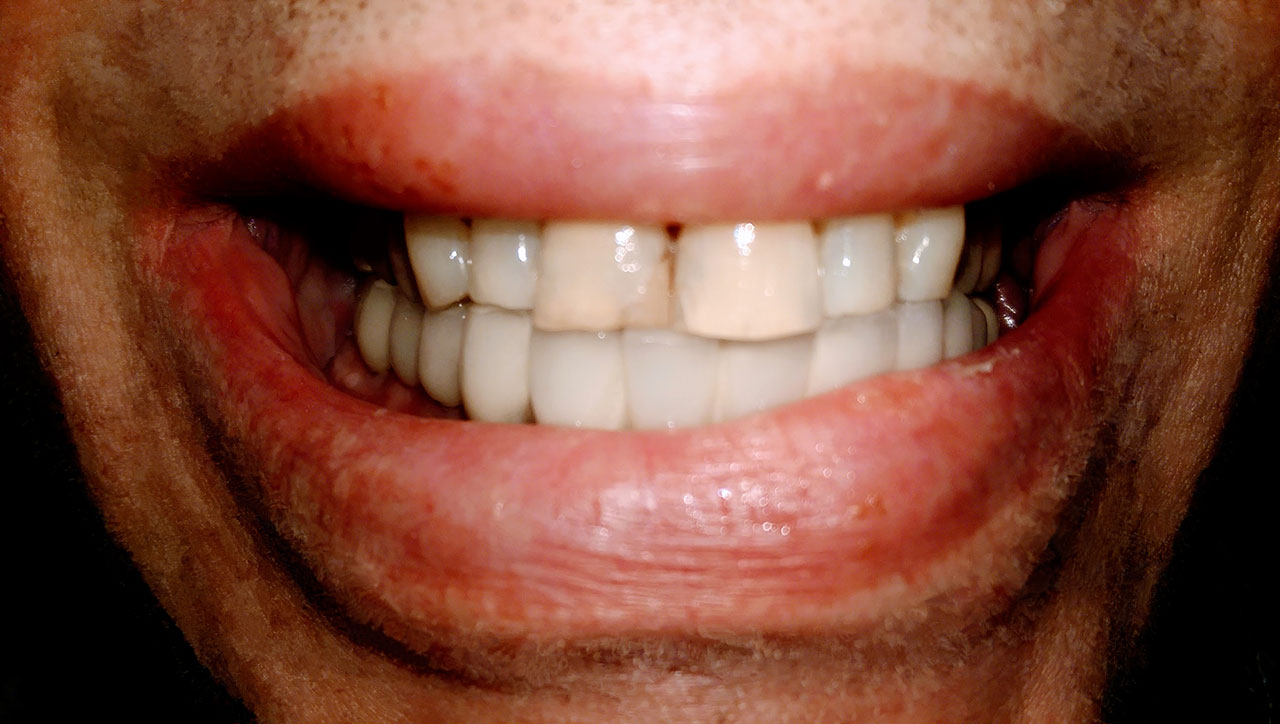

Teljes fogatlanság helyreállítása 2 nap alatt

Teljes fogatlanság helyreállítása 2 nap alatt azonnal terhelhető svájci IHDE implantátumokkal és PMMA műanyag hidakkal. Intraorális szkennerrel vettünk lenyomatot az implantáció után, és erre a digitális mintára készítette el a fogtechnika a hidak digitális tervezését, majd faragta ki műanyagból. Ezt a gyors munkát az azonnal terhelhető implantátumok és a digitális lenyomat, tervezés segítségével tudtuk megcsinálni mindössze 2 nap alatt. Dr. Kelemen Péter és a Symbion Fogtechnika munkája.